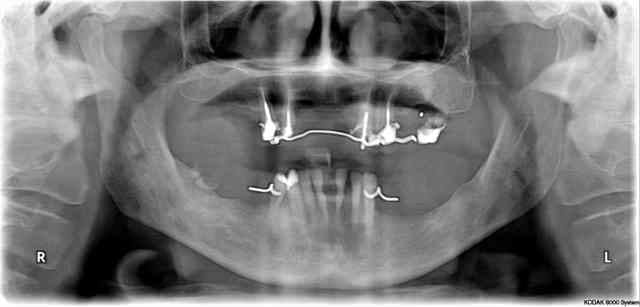

(je joins la pano et deux photos, je précise qu'en rétroalvéolaire, les racines antérieures et prémolaires en haut sont "bonnes" même si la dépose de magnifiques RCR compos infiltrés donne l'illusion du contraire)

HAIG, les racines en question ne présentent pas d'infection, pas d'obstacle au retraitement et une longueur suffisante pour espérer s'en servir.

Globalament, il avait effectivement entrepris un bridge. y a au moins une paire d'années. Et c'est de rester en provisoire pendant tout ce temps qui fait qu'il a perdu des piliers.

Vous avez quoi avec le chiffre 4 ? j'ai 5 piliers en haut (15 13 23 24 25).